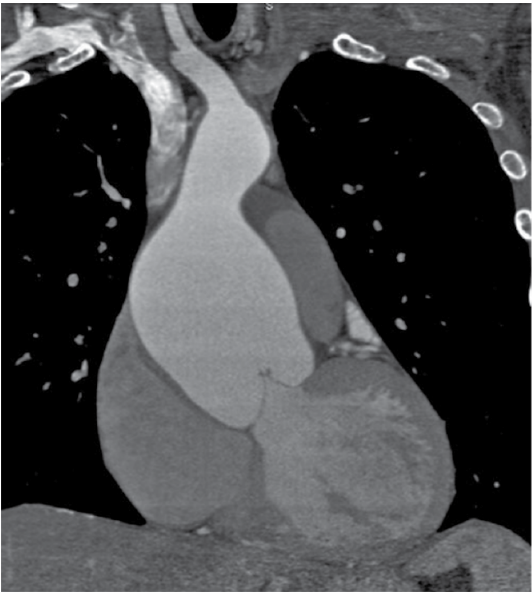

Homem, de 35 anos, apresenta quadro de dor nas costas sendo submetido ao exame mostrado a seguir.